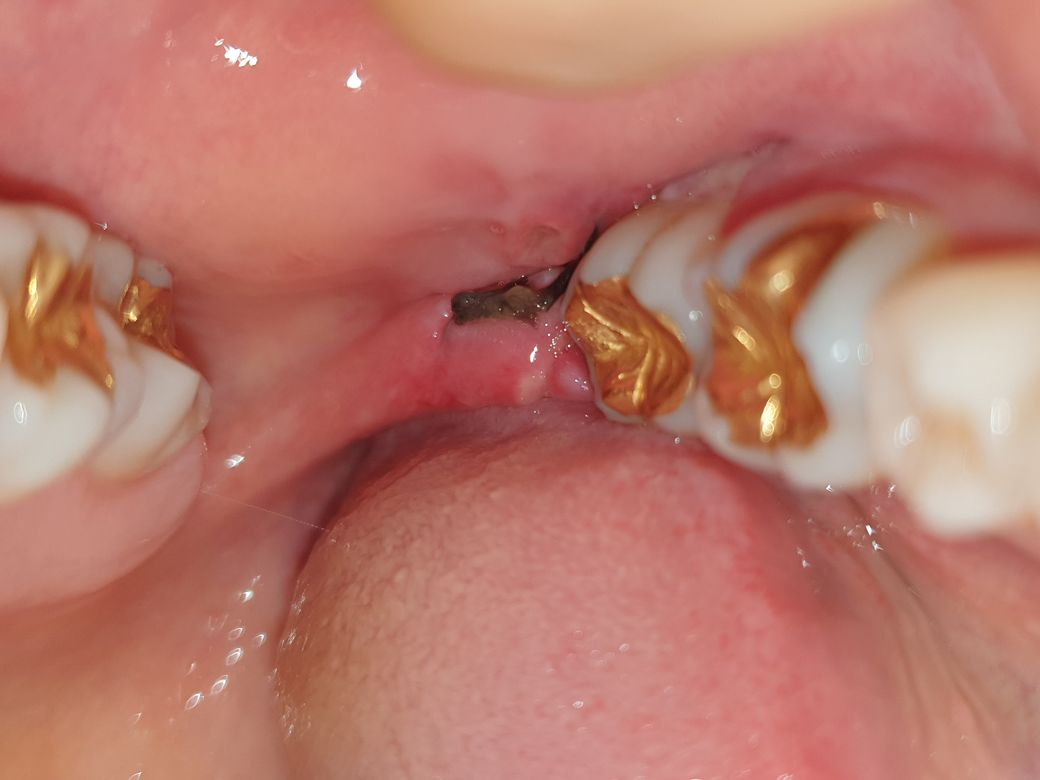

매복사랑니 발치 후 (사진주의) 상태문의

월요일 저녁에 매복 사랑니를 발치하였습니다.

1. 여전히 아파서 붓기가 좀 빠져서 거울을 들여다보니 사랑니 뽑은 곳 옆 볼은 구멍이 난거같은데 염증일까요?

2. 검은실 옆쪽 꼬맨부분 주변 흰색이 아픈데 그것도 혹시 염증인가요?

궁금하고 아파서 올려봅니다 ~~ 실밥은 다음주 수요일에 뽑습니다.

• 1번 째 사진

발치후 정상적으로 잇몸이 아물고 있는것으로 보입니다. 사랑니를 발치한 부위에는 혈병이 생기면서 발치부위를 보호해 주기때문에 치유가 일어나게 됩니다.

사진으로 봤을 때, 사랑니를 뺴고 봉합을 했으며, 볼쪽의 구멍은 단순 구내염이나, 발치시 상처가 아물고 있는것으로 보입니다.

흰색으로 있는것은, 발치부위 상처이며, 낫는 중이니 크게 문제될 것은 없습니다.

사랑니 뽑은 자리 주위로 염증이 발생한 상태로 보입니다. 치유 과정 중에서도 염증 반응이 나타나기 때문에 이는 정상 범주로 볼 수 있으나, 베체트 병이 있는 경우 구내염이 쉽게 생길 수 있는 상태로, 발치 주변 잇몸에 구내염이 같이 발생했을 가능성이 있어 보입니다.